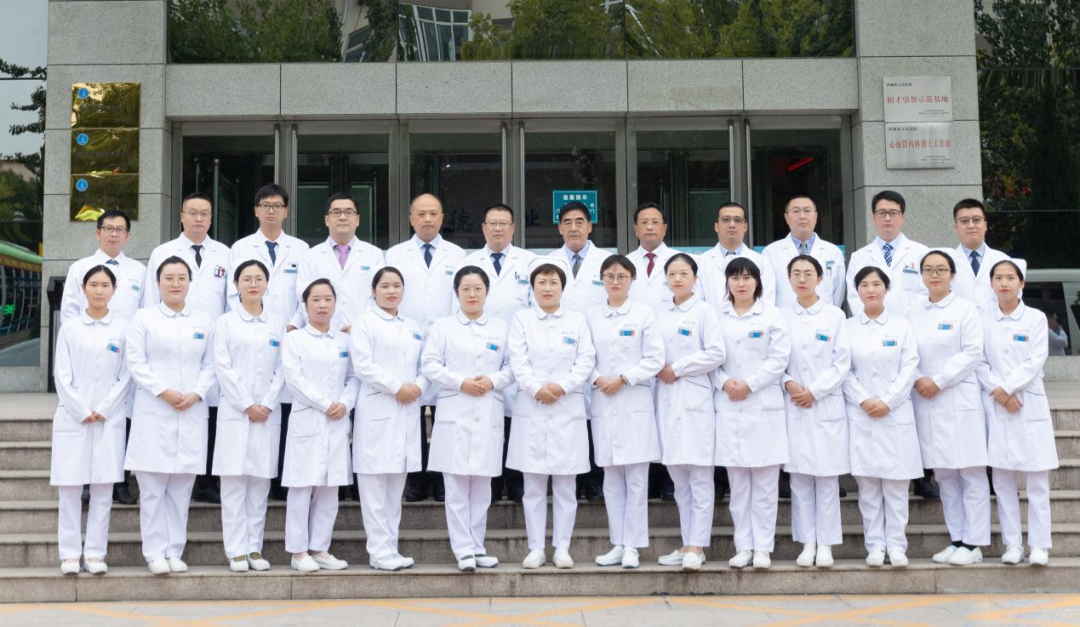

张双卫

医学硕士,主任医师,普外科二病区主任

樊光明

主任医师,普外科二病区副主任

孙晓刚

医学硕士,副主任医师

武亚嘉

山西省医师协会外科医师分会委员、山西省医师协会整合医学专委会委员、山西省医师协会肝癌专委会委员、山西省专家学者协会医学分会普外科专委会青年委员。